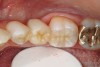

Figure 6a  Missing mandibular premolar; the patient has declined the placement and restoration of missing tooth with an implant. The clinical decision was for a fiber FPD.

Figure 6a

Figure 6b  Sizing instrument to prepare the proximal box to an adequate width for the Tescera quartz fiber U-Beam.

Figure 6b

Figure 6c  Inlay preparations of abutment teeth for a FPD.

Figure 6c

Figure 6d  From this facial view, the opaque U-Beam is apparent in the gingival aspect of the proximal portion of the restoration.

Figure 6d

In vitro studies have demonstrated that the use of unidirectional glass-fiber reinforcement in the connector areas of FPDs contributes to significant composite reinforcement.29,36-38,66-68 Similar findings have been reported with a leno-weave UHMWPE and triaxial weave UHMWPE fiber.20,33,36 Fiber-reinforcing materials used by a dental laboratory are either resin pre-impregnated glass fibers, pre-polymerized composite resin surrounding glass fibers, biaxial braid UHMWPE, leno-weave UHMWPE, or a triaxial weave UHMWPE (Table 3). Typically, the preparation designs for the abutment teeth are inlay or onlay preparations (Figure 6A through Figure 6D). They are highly successful and can provide the patient with clinical service for more than 5 to 10 years.69 These restorations must be cemented using an adhesive resin technique with resin cements. Both etch-and-rinse adhesives with a self-cure or dual-cure composite resin cement or with a self-adhesive resin cement are indicated for cementing these restorations (Figure 7).36-38,70 Also, fiber-reinforcing materials are being used by dental laboratories in the fabrication of provisional restorations to reinforce and strengthen acrylic and composite-resin provisional materials.15,40,71